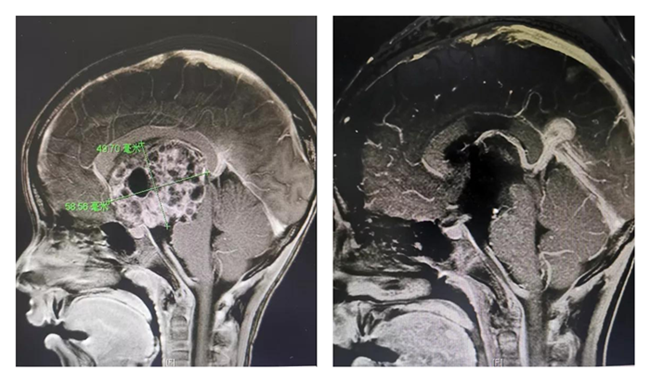

手术前后

左图为术前,右图为术后